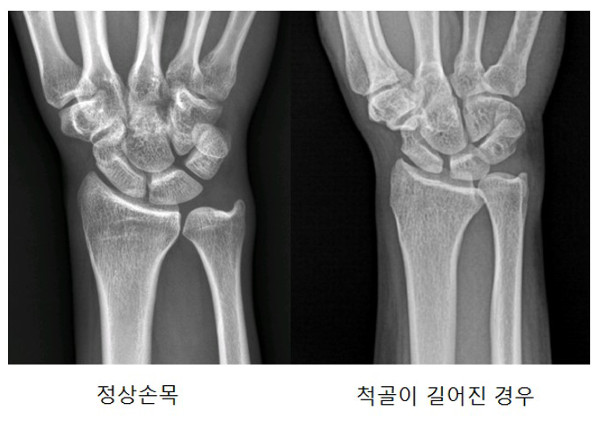

왼손바닥을 바닥을 보게 하고 엑스레이를 찍으면 손목과 팔꿈치 사이 오른쪽에 좀 굵은 뼈가 요골이고 왼쪽에 좀 얇은 뼈가 척골인데요. 척골과 요골의 길이가 손목쪽 끝이 미묘하게 조금 차이가 납니다만 일반적으로 거의 동일하면 정상이고 척골이 좀더 길면 양성변이라고 해서 충돌증후군이 발병하고 통증이 생깁니다.

엑스레이 결과를 보면 필자는 왼손 오른손 모두가 선천적으로 척골이 좀 길었습니다. 특히 왼손은 과거 손상 이력(기억은 안납니다) 이 있어 비정상 돌기까지 더해 더욱 길었습니다. 아래 사진은 오른손이긴 합니다만 이해를 위해 참조했습니다.

척골이 길어지면 손목하단의 여러 뼈들과 척골 사이의 공간이 비정상적으로 좁아지고 그 공간에 있던 조직들이 여기저기 부딪치며 염증이 발생하며 통증이 생깁니다.